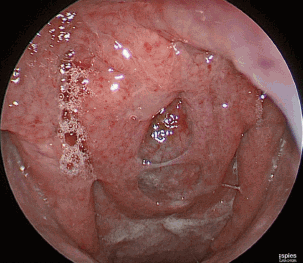

외래에서 시행한 비강 내시경 소견은 다음과 같다.

위 병변에 대해 조영증강 CT 검사를 시행하였으며, 조영 증강되지 않는 12×16 mm의 낭성 종괴가 비인강 상부에 확인되었다.